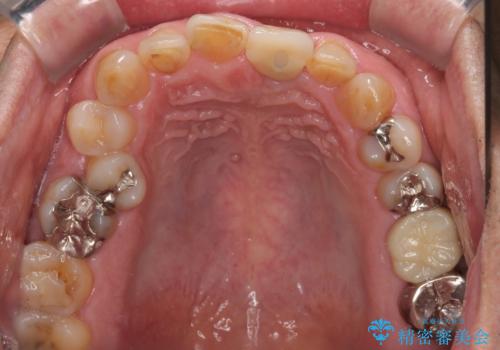

歯肉形態を概ね回復するタイミングでインプラントを埋入し、補綴治療を行うこととしました。

歯肉移植術による更なる歯肉ラインの改善も検討しましたが、笑ったときに歯肉ラインは唇に隠れてしまうため、現在の位置にて仕上げることとしました。

骨の前後幅が小さかったため、細いインプラントを選択せざるを得ない状況でした。咬合力が非常に強い方のため、就寝時のマウスピース装着を徹底していただき、インプラントへの負担を軽減することとしています。